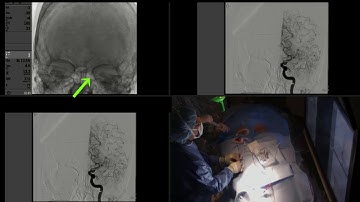

How to do Mechanical Thrombectomy? - Basic steps of Solumbra Technique